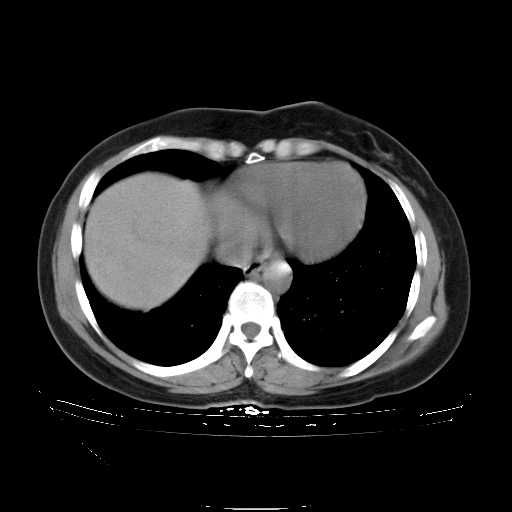

下面是今天刚刚做的,在上海治疗,吃了家属也说不清的一种药,一个月1万左右,

考虑  腺癌肺内转移,治疗较前病灶缩小、减少

肺癌并肺内转移,这种疾病治疗后在影像上看略有好转,不是很显著,但是肿瘤治疗效果影像只是一方面。

支持右肺下叶周围型肺癌并肺内淋巴管炎,  原发灶小了,但转移较前片明显了.。

支持右肺下叶周围型肺癌并肺内淋巴管炎;病灶有所控制。